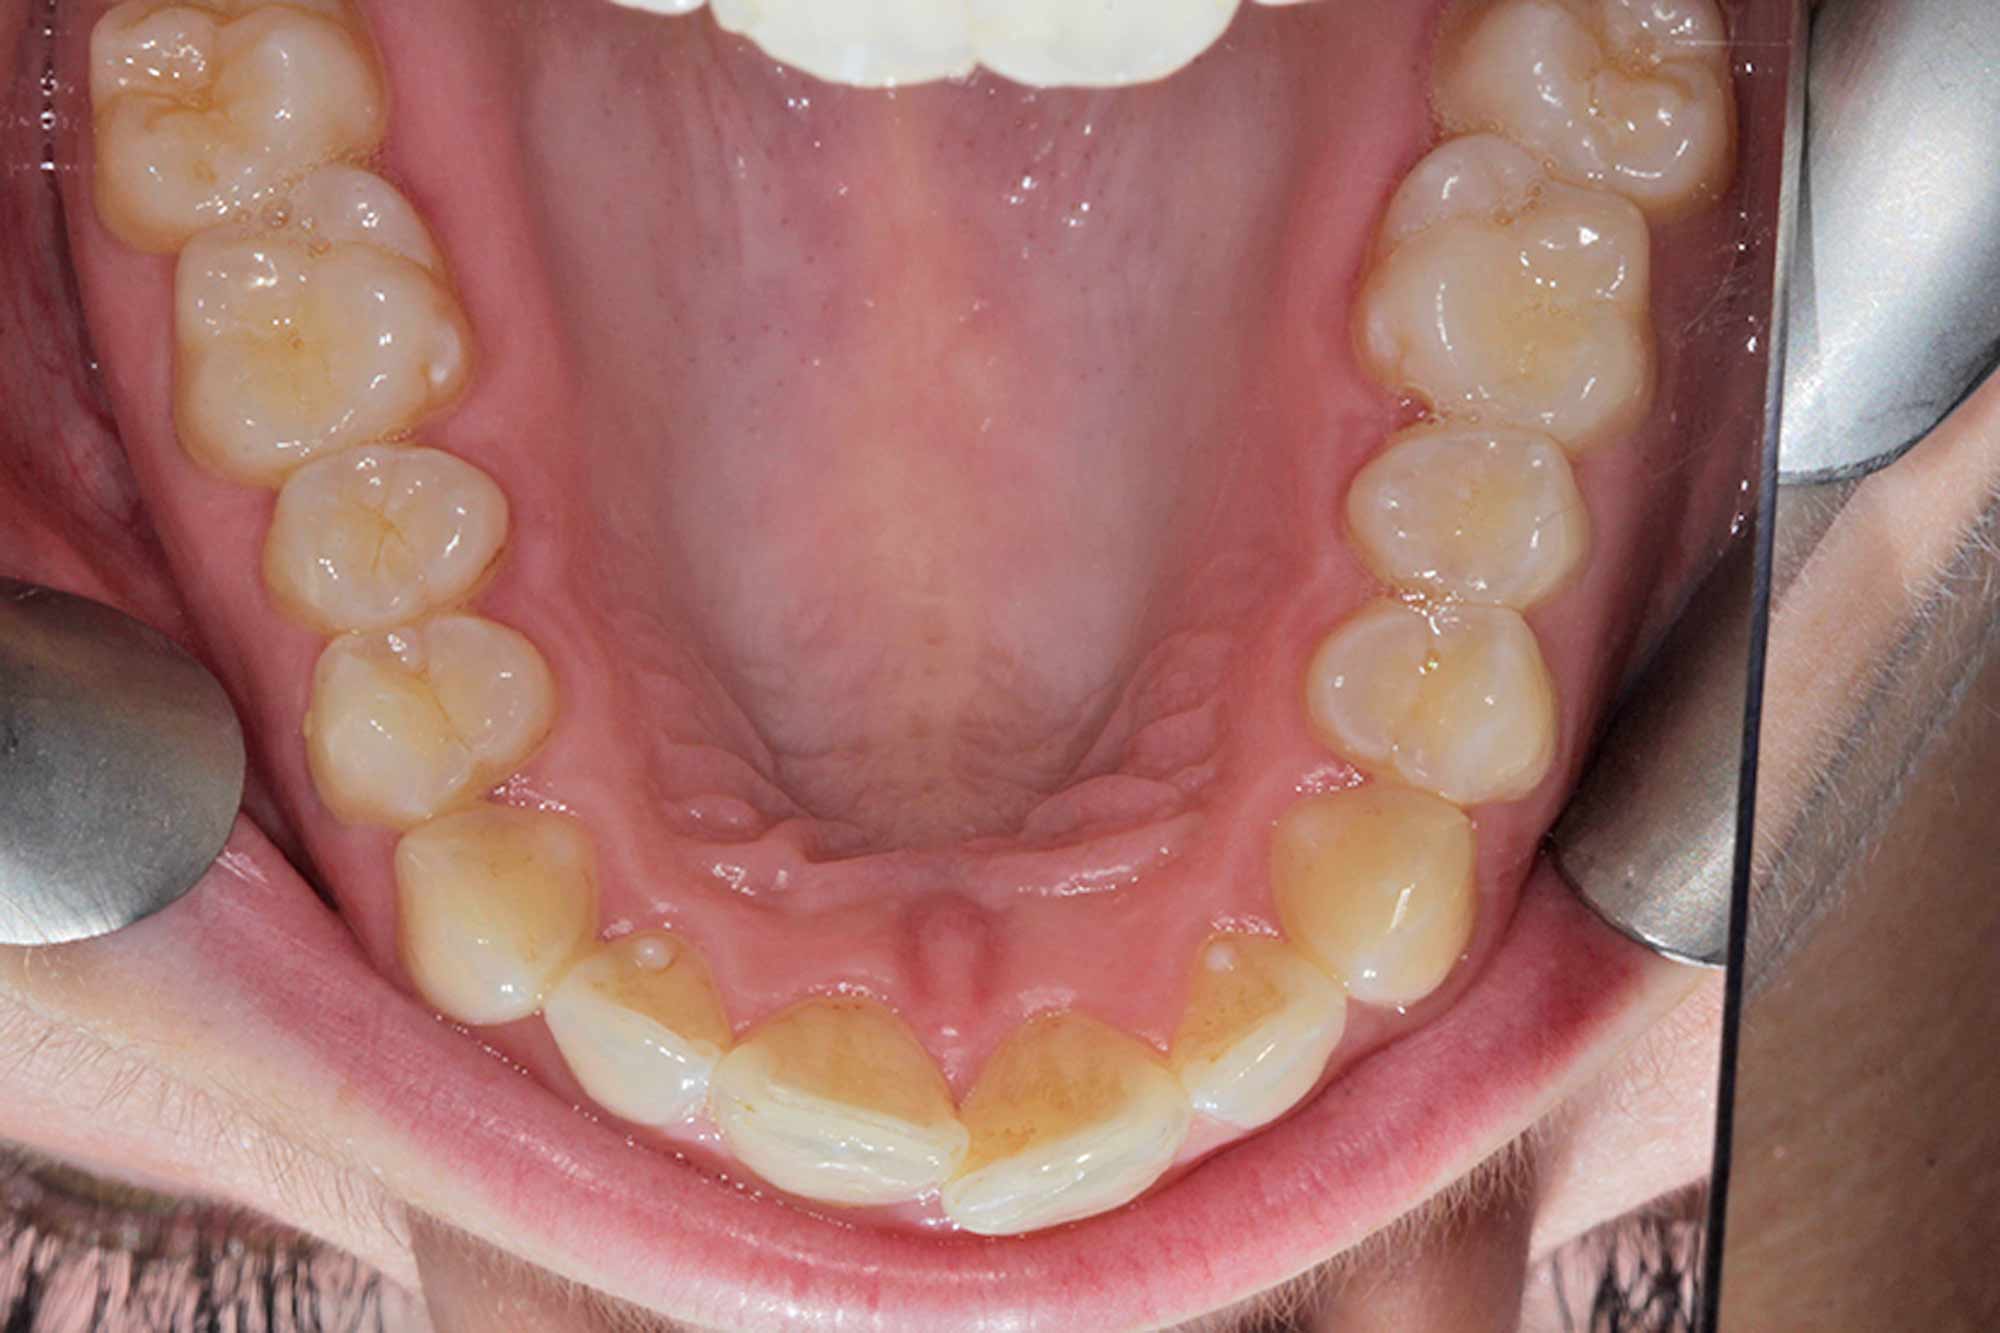

Bond

Once the tooth positioning and colour were both at an exemplary stage, it was time to frame the result with composite direct edge bonding. This has been made much easier due to all the other factors. Our restorative material of choice for this case was Venus Pearl shade BL. This matched the patient’s newly whitened teeth perfectly.

The other factors had been carried out to such a high level, that the bonding stage was very straightforward and fairly easy to conduct. Using the right tools to blend the margins in and polish them to give this case even more longevity in the long run. The key to these cases is anatomy. Match the anatomy and proportions, and it will blend beautifully.

Outcome

The final result was another delighted patient and another beautiful smile completed following all the smile design protocols. This can incorporate any system needed as long as your planning process is sound and predictable each time.